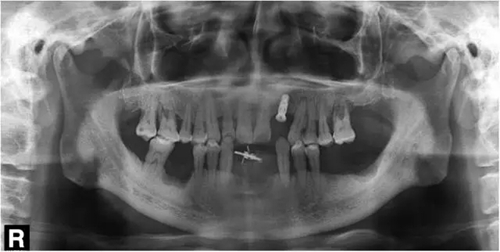

圖4 種植術(shù)后影像學檢查

3個月后,分別使用傳統(tǒng)的轉(zhuǎn)移桿硅橡膠取模以及口內(nèi)掃描取模進行修復(圖5~8)。